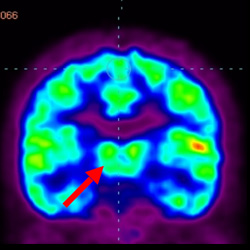

細(xì)胞治療前PET CT掃描顯示神經(jīng)組織中的藍(lán)/黑色區(qū)域,表明腦癱引起的大腦損傷。

腦癱細(xì)胞療法, 腦癱治療

細(xì)胞治療后,藍(lán)色和黑色區(qū)域減少,并且看到更活躍的區(qū)域。這表明損傷減少并改善了大腦功能。